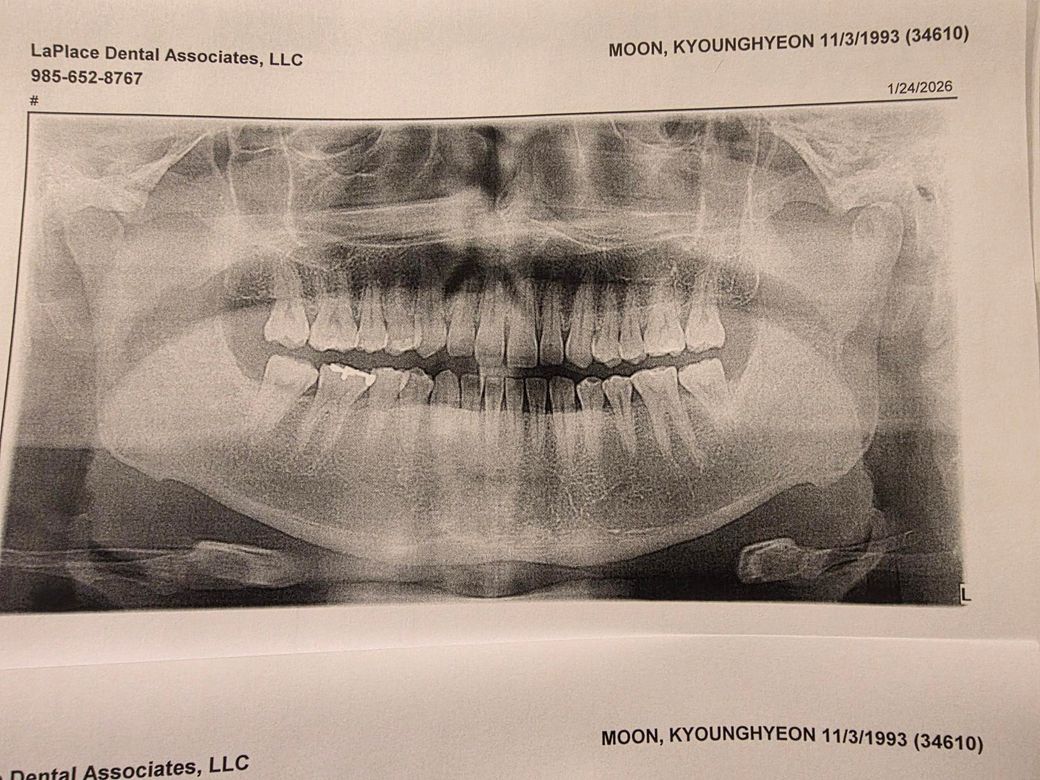

미국에서 치과 진료받은 기록좀 봐주세요

어금니에 2/3가 금이 간 상황인데 어때보이냐니까 자꾸 다른병원갔다가 오래요 느낌에 과잉진료같은데 이거 이정도면 치아를 어떻게 해야하는게 맞나요? 사진상 보철물 반대편인 우측 세컨드 몰러입니다

• 1번 째 사진